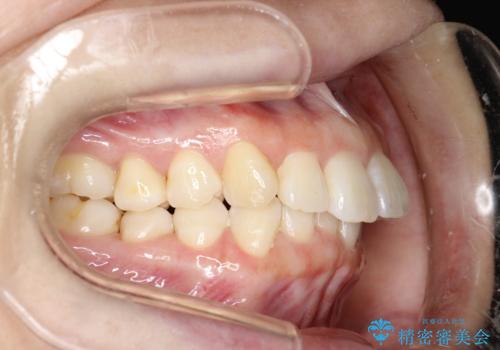

インビザライン ライトパッケージによる部分矯正治療 下の前歯のみの歯並び改善

- インビザライン ライトパッケージパーシャル(下顎のみ)

- 下の前歯の歯並びのみの改善をご希望されました。

インビザライン ライトパッケージ下顎のみ(1枚~14枚まで)での治療を行なっていきました。

マウスピース枚数 初回14枚 + 追加13枚

概ね7ヶ月で治療完了しました。

インビザラインのライトパッケージでは14枚までという枚数制限がありますが、限られた枚数の中で当院独自の工夫を随所に盛り込み、狙い通りの治療結果が得られました。